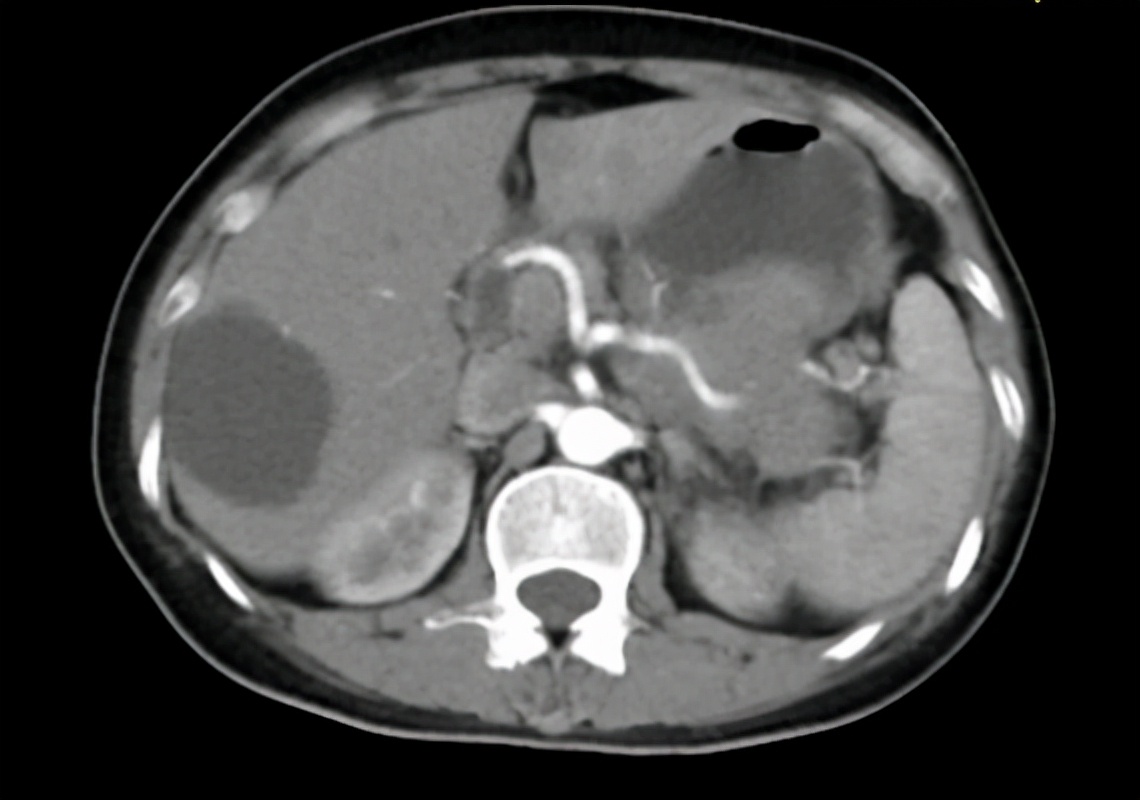

这是一位52岁的中年女患者,因右中上腹部疼痛伴反酸、烧心5月余,先后于深圳市西丽医院、罗湖区人民医院就诊,未能明确诊断,2018年6月至深圳市某人民医院就诊,行腹部彩超提示胰腺尾部占位,肝脏多发结节;2018-6-5*警武**医院PET-CT提示:胰腺尾部占位,大小6×7cm cm,侵犯胃后壁及左肾上腺,恶性肿瘤可能性大,腹膜转移瘤可能,肝脏多发转移可能。2018-6-14于中山大学附属第七医院行超声内镜引导下胰尾穿刺活检,病理回报:胰尾鳞状细胞癌。初步诊断:1、胰腺尾部鳞状细胞癌(cT4N1M1)2、肝多发转移瘤3、多发淋巴结转移。

图1:患者2018年6月的CT图,红框为胰腺尾部原发灶,大小约6×7cm。